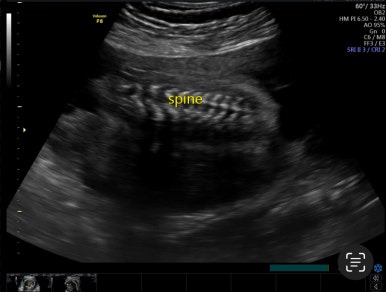

21주 1일

정밀초음파로 외형, 장기 등이 이상이 없는지 확인하는 시기이다.

머리부터 발끝까지 꼼꼼하게 검사를 하게 된다!